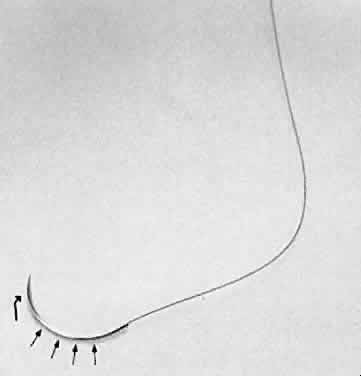

One potential problem with scissors is the tendency to produce a serrated

edge. When the scissors are advanced and the direction of the cut is

changed, or the tissue is compressed, a serrated edge results (Fig. 25). When the scissors' tips are closed completely, they penetrate completely

into the tissue and produce a small lateral cut.4  Fig. 25. When scissors are used to cut tissue, it is important to avoid producing

a serrated effect. A. Scissors are closed partially (arrows), reopened carefully, and advanced following the original direction of

the cut. B. When the tips are closed completely, they will penetrate tissue and act

as a cutting edge, producing a small lateral cut. This movement causes

a serrated effect. Fig. 25. When scissors are used to cut tissue, it is important to avoid producing

a serrated effect. A. Scissors are closed partially (arrows), reopened carefully, and advanced following the original direction of

the cut. B. When the tips are closed completely, they will penetrate tissue and act

as a cutting edge, producing a small lateral cut. This movement causes

a serrated effect.

When using scissors to cut tissue, it is preferable to avoid producing

a serrated edge. This may be avoided if scissors are closed partially, reopened, and

carefully advanced in the original direction of the cut. Without

removing the scissors from the wound, the blades are reapplied

to the tissue and again opened and advanced in the original direction

of the cut. This maneuver is important when making a large incision, such

as in corneal transplantation or large incision cataract extraction. Therefore, when

scissors are used to create a limbal wound, the

inferior blade is inserted into the anterior chamber and the scissors

are compressed partially, released, and advanced. Care must be taken to

avoid changing the direction of the cut, closing the scissors completely, or

removing the scissors from the wound before completion. Using

this technique will avoid an irregular serrated incision. All spring-handled scissors are designed such that applying pressure on